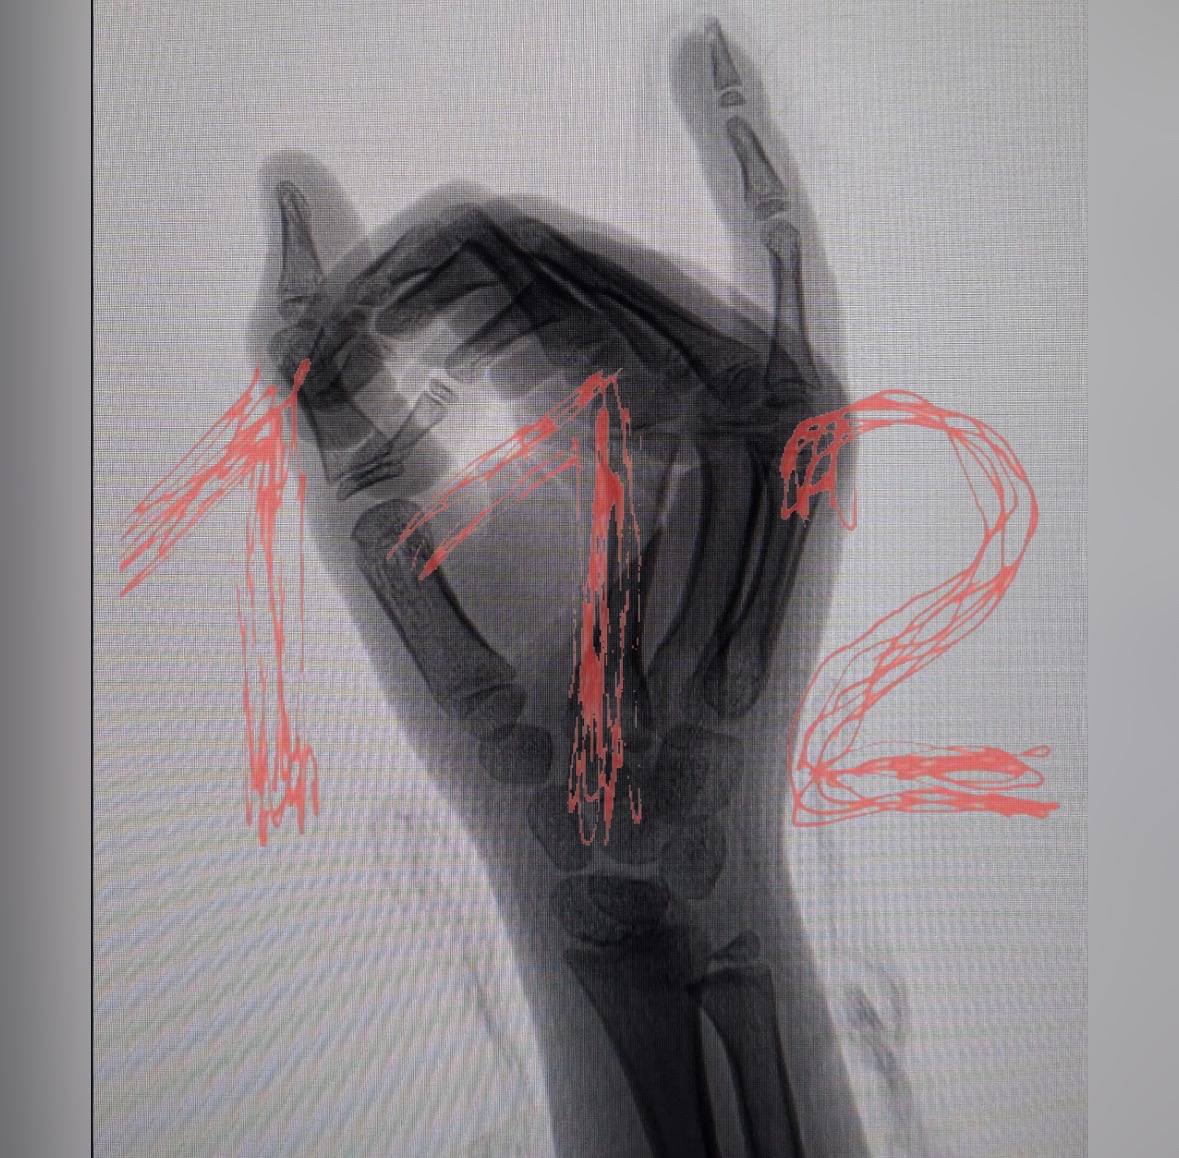

Сотрудники детского сада, по утверждению матери, не вызвали скорую помощь, ограничившись сменой повязки. Родителям сообщили, что без их присутствия вызвать медиков нельзя. Девочку доставили в больницу, где ей наложили швы, однако травма оказалась серьезнее, чем предполагалось. Сейчас ребенку грозит ампутация пальца из-за повреждения кости.

Руководство детского сада до сих пор не связалось с семьей пострадавшей. Родители продолжают обращаться в различные медицинские учреждения в поисках помощи. Ситуация вызвала широкий общественный резонанс и требует тщательного разбирательства.